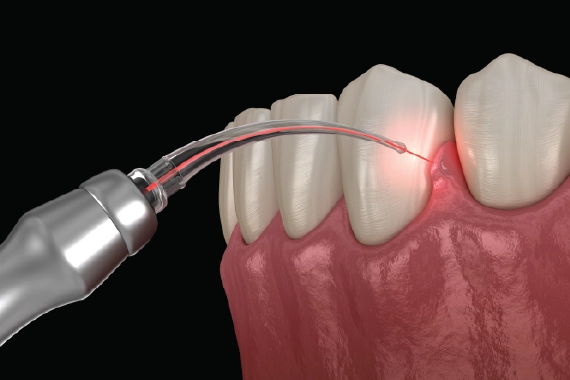

Soft Tissue Laser Technology

At Pan Family Dentistry and Implants, we are proud to offer the latest in dental technology to provide our patients with the most effective, comfortable, and efficient treatments available. One of the key innovations we utilize is Soft Tissue Laser Technology, which enables us to perform various dental procedures with unmatched precision and minimal discomfort.

What Is Soft Tissue Laser & What Are The Benefits?

Soft tissue lasers are used in a variety of dental treatments involving the gums and soft tissues of the mouth. The laser delivers concentrated light energy to target specific areas, allowing for precise, minimally invasive procedures that promote faster healing and better results. Unlike traditional methods that often require scalpels or sutures, soft tissue lasers provide a gentle approach that reduces the need for cutting and stitching, enhancing both patient comfort and recovery time.